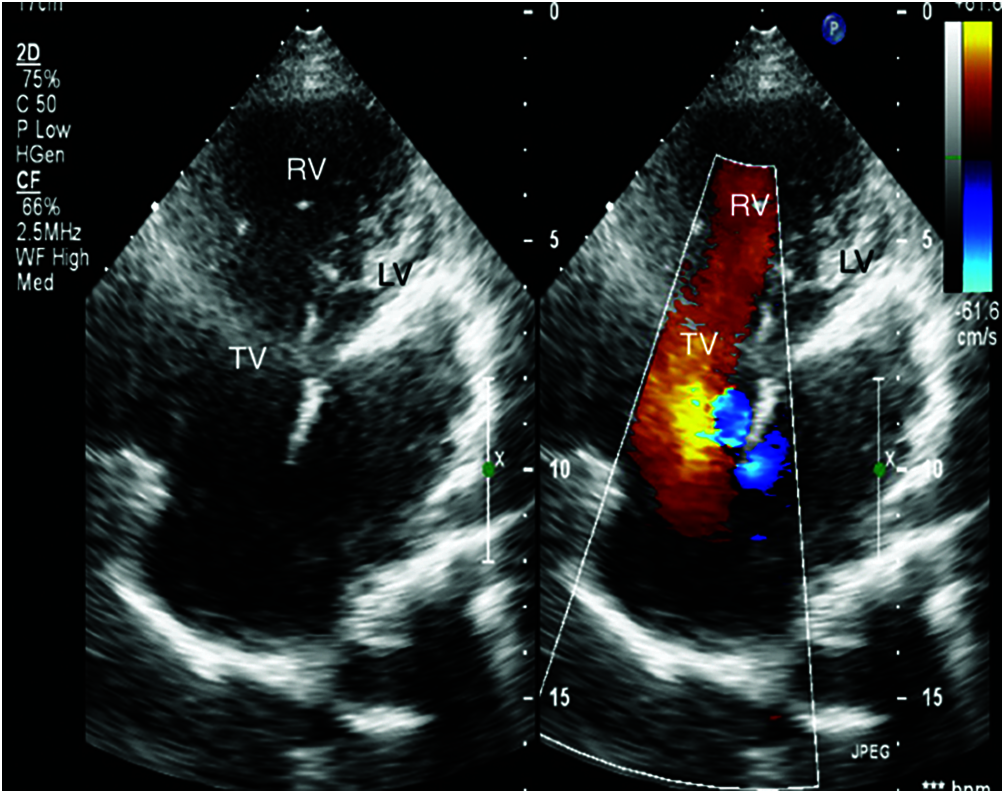

Full ECG gated echocardiographic study using echocardiography machine with phased array transducer of suitable frequency to perform sequential segmental analysis (Figs. 1 and 2).

Figure 2: Apical 4 chamber view showing mitral atresia in patient number 15 (TV: Tricuspid valve, LV: left ventricle, RV: right ventricle)